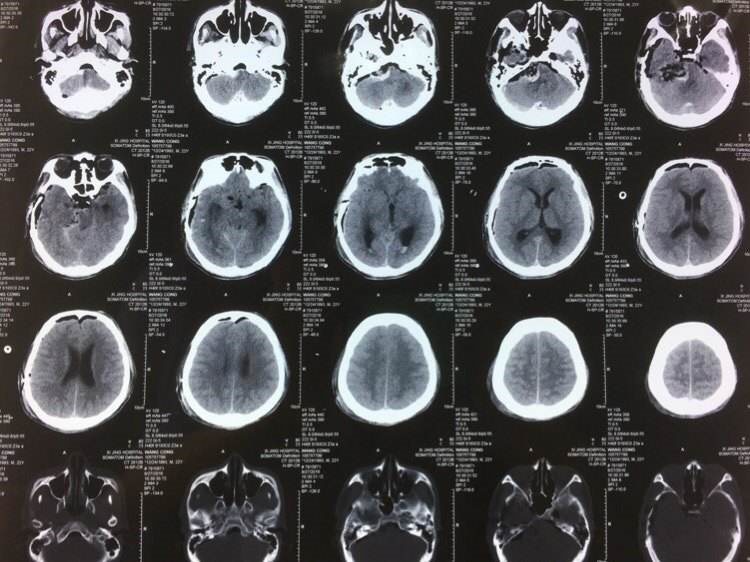

三叉神经鞘瘤发生在三叉神经半月神经节处,肿瘤亦可同时向三叉神经根部延伸,常分为三型:中颅窝型、骑跨型和后颅窝型。MR表现中颅窝型及后颅窝型肿瘤常为圆形或类圆形。表现为偏一侧生长的鞍旁及桥小脑角同时有肿瘤存在而呈“哑铃状”,呈现跨颅窝生长表现。特征性表现为三叉神经增粗与肿瘤相连续、Meckel腔扩大、颞骨岩部骨质吸收或损害、跨越中后颅窝呈骑跨式生长。

三叉神经鞘瘤的影像学表现

1、T1W I呈均匀或不均匀等低信号,T2W I多呈不均匀高信号。MR I增强后多呈不均匀明显强化,但也可完全均匀强化。

2、肿瘤沿着三叉神经径路生长,跨颅窝哑铃状为特征性表现。三叉神经根部增粗与瘤体相连续是诊断三叉神经瘤的可靠征象。

3、常伴有岩骨的骨质吸收,肿瘤边界清,周围脑组织多无水肿及钙化。但瘤体较大时可压迫邻近脑组织引起静脉回流障碍性水肿治疗及预后。